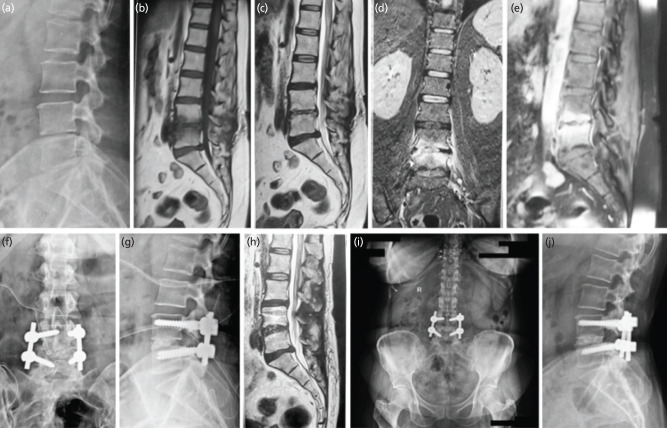

Material and methods: Retrospective analysis of patients operated by transforaminal lumbar interbody fusion (TLIF) in POS was done. Confirmed clinico-radiological diagnosed POS cases, not responding within three to four weeks were included. Normalisation of CRP and radiological stable reconstruction was assessed for objective clearance of POS and bony union.

Results: Ninety-five patients were included in the study with minimum follow-up period of two years. The mean age was 51.63±13.63 years. There were organisms cultured in 55 patients (57.89%). The ODI improvement of the patients was noted to improve from 88.71±5.3 to 20.80±9.7 (8 weeks) and was incremental at 2 years follow-up (10.12±6.41) and maintained further at final follow-up at 9±4.3. Bony union achieved in all with stable reconstruction. The resumption of activities of daily living (ADL) was quick (15.90±8.20 days) and job (3.67±1.31 months) was achieved in all the patients. In poor outcomes, two patients didn't respond, and one patient died due to uncontrolled infection.